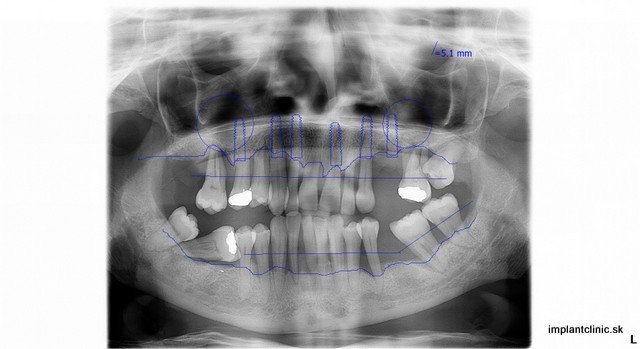

Na kompletnú rekonštrukciu Pavlinho chrupu bolo potrebných 24 extrakcií, 12 zubných implantátov, 2 x sinus lift, 12 implantátových koruniek v sánke a 12 implantátových koruniek vo vrchnej čeľusti. Zdravie našich zubov ovplyvňuje naše celkové zdravie, ale aj kvalitu nášho života. Pokazené zuby nie sú len estetický problém. Prepojenie medzi stavom chrupu a našim zdravím je oveľa väčšie, ako si myslíme. Zápaly v ústnej dutine sa krvnou cestou dostávajú do celého tela a môžu spôsobiť ďaľšie problémy. Odkladanie návštevy zubného lekára môže spôsobiť to, že zuby sa pokazia natoľko, že o ne prídeme. Tým sa zmení aj kvalita nášho života. Bezzubá čeľusť je vážny estetický nedostatok, ktorý si všimneme na ľuďoch hneď ako začnú rozprávať.

Naša pacientka Pavla mala ešte všetky svoje zuby, no tie z hľadiska dlhodobej prognózy už nebolo možné ponechať. Preto boli všetky zuby extrahované. Hneď po extrakcii sa na vrchnú čeľusť a sánku zaviedlo po 6 zubných implantátov. Implantáciu vykonal náš hlavný implantológ MUDr. Marek Salka.